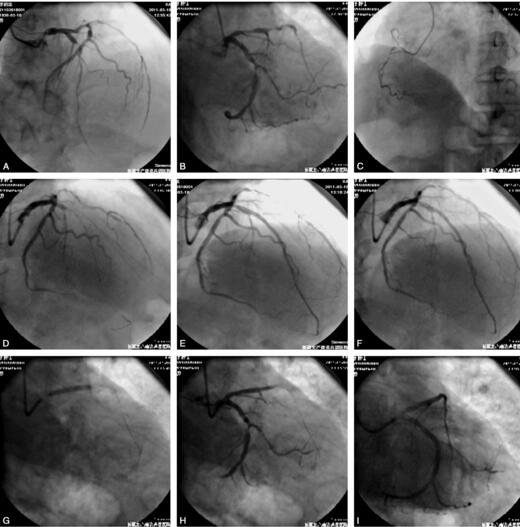

入院查体:血压140/80mmHg心率78次/分。实验室检查:心肌酶入院后10小时达最高峰:CK 2171U/L,CK-MB 213U/L,LDH 460U/L;肌钙蛋白>2ng/ml。入院当天再次出现胸痛,持续20分钟,生命体征平稳,心电图演变见图1A,图1B。心脏彩超示:室间隔心尖段心肌回声偏强,EF:54%。诊断:冠心病急性广泛前壁心肌梗死KillipⅠ级。给予冠心病药物强化治疗,此后患者症状缓解,药物治疗10天后行PCI治疗。CAG结果:LAD近中段85%~90%弥漫性狭窄;LCX近中段80%~85%节段性狭窄;RCA细小,近中断90%节段性狭窄。手术过程:先于前降支中段置入1枚乐普2.5mm×36mm支架,释放完毕后患者开始出现胸痛,心电图提示胸前导联ST抬高,造影示近段狭窄加重,给硝酸甘油后缓解,于近段置入1枚乐普3.0mm×24mm支架,患者胸痛再次发作,且明显加重,伴血压下降,造影示前降支近段至开口狭窄加重,血流缓慢,TIMI 2级,于开口处置入1枚乐普3.5mm×24mm支架,但患者胸痛无明显缓解;造影回旋支中段第一钝缘支开口处狭窄加重,考虑痉挛,给予硝普钠等冠脉内静推,同时给多巴胺升压,替罗非班5ml冠脉内静推,疼痛有所缓解,遂于回旋支中段置入1枚乐普4.0mm×29mm支架,造影显示慢血流,患者仍有胸痛,但有所减轻,观察15分钟后血压心率均恢复正常,结束手术。返回病房途中患者突然出现呼吸心跳骤停,立即心肺复苏,心电图如图1C,抢救1小时无效死亡。造影及支架置入过程见图2。

图2 A~C.LAD近段85%以上节段性狭窄,LCX中段75%狭窄,右冠细小并近中段95%狭窄;D~I.前降支及回旋支支架置入过程